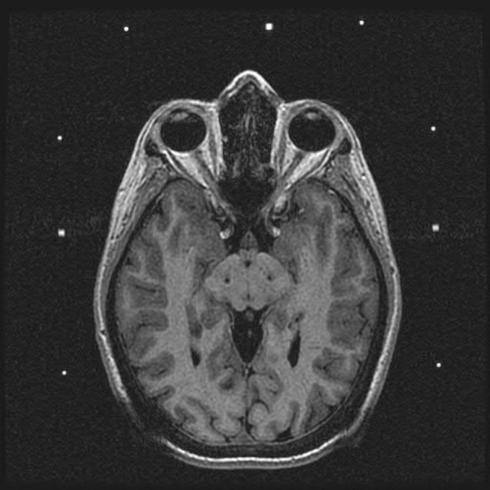

The modern era of stereotactic and functional neurosurgery has ushered in state of the art technologies for the treatment of movement disorders, particularly Parkinson's disease (PD), tremor, and dystonia. After years of experience with various surgical therapies, the eventual shortcomings of both medical and surgical treatments, and several serendipitous discoveries, deep brain stimulation (DBS) has risen to the forefront as a highly effective, safe, and reversible treatment for these conditions. Idiopathic advanced PD can be treated with thalamic, globus pallidus internus (GPi), or subthalamic nucleus (STN) DBS. Thalamic DBS primarily relieves tremor while GPi and STN DBS alleviate a wide range of Parkinsonian symptoms. Thalamic DBS is also used in the treatment of other types of tremor, particularly essential tremor, with excellent results. Both primary and various types of secondary dystonia can be treated very effectively with GPi DBS. The variety of anatomical targets for these movement disorders is indicative of the network-level dysfunction mediating these movement disturbances. Despite an increasing understanding of the clinical benefits of DBS, little is known about how DBS can create such wide sweeping neuromodulatory effects. The key to improving this therapeutic modality and discovering new ways to treat these and other neurologic conditions lies in better understanding the intricacies of DBS. Here we review the history and pertinent clinical data for DBS treatment of PD, tremor, and dystonia. While multiple regions of the brain have been targeted for DBS in the treatment of these movement disorders, this review article focuses on those that are most commonly used in current clinical practice. Our search criteria for PubMed included combinations of the following terms: DBS, neuromodulation, movement disorders, PD, tremor, dystonia, and history. Dates were not restricted.